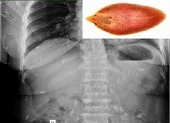

Ngày 2-12, tin từ BV Chợ Rẫy (TP.HCM) cho biết vừa thực hiện nội soi gắp một con sán dây bò có chiều dài hơn 1 m trong ruột người đàn ông (56 tuổi, ngụ Đồng Nai).

Trước đó, bệnh nhân đến BV Chợ Rẫy để khám bệnh và được nội soi tiêu hóa. Tại Khoa nội soi, các bác sĩ phát hiện ra bệnh nhân có một con sán dây bò đang trú ngụ trong tá tràng và kéo con sán ra.

Tuy nhiên, do đầu sán bám rất chắc nên chỉ kéo ra được giữa chừng...

Con sán được gắp ra từ cơ thể người đàn ông. Ảnh: BVCC

Bệnh nhân tiếp tục được cho dùng thuốc xổ để đẩy con sán ra ngoài hoàn toàn. Ông cho biết thêm có thói quen ăn bò tái từ nhỏ, khi ăn chỉ vắt chanh và chế nước sôi vào thịt chứ không nấu chín.

Con sán dây bò được lấy ra nhưng phần đầu vẫn còn nằm trong cơ thể người đàn ông. Ảnh: BVCC

BS Tăng Trung Hiếu, Khoa nội soi BV Chợ Rẫy, cho biết sán dây bò trưởng thành có thể dài 2-4 m, thân có 800-1.000 đốt sán trắng dẹt, có thể phát hiện các đốt sán qua phân.